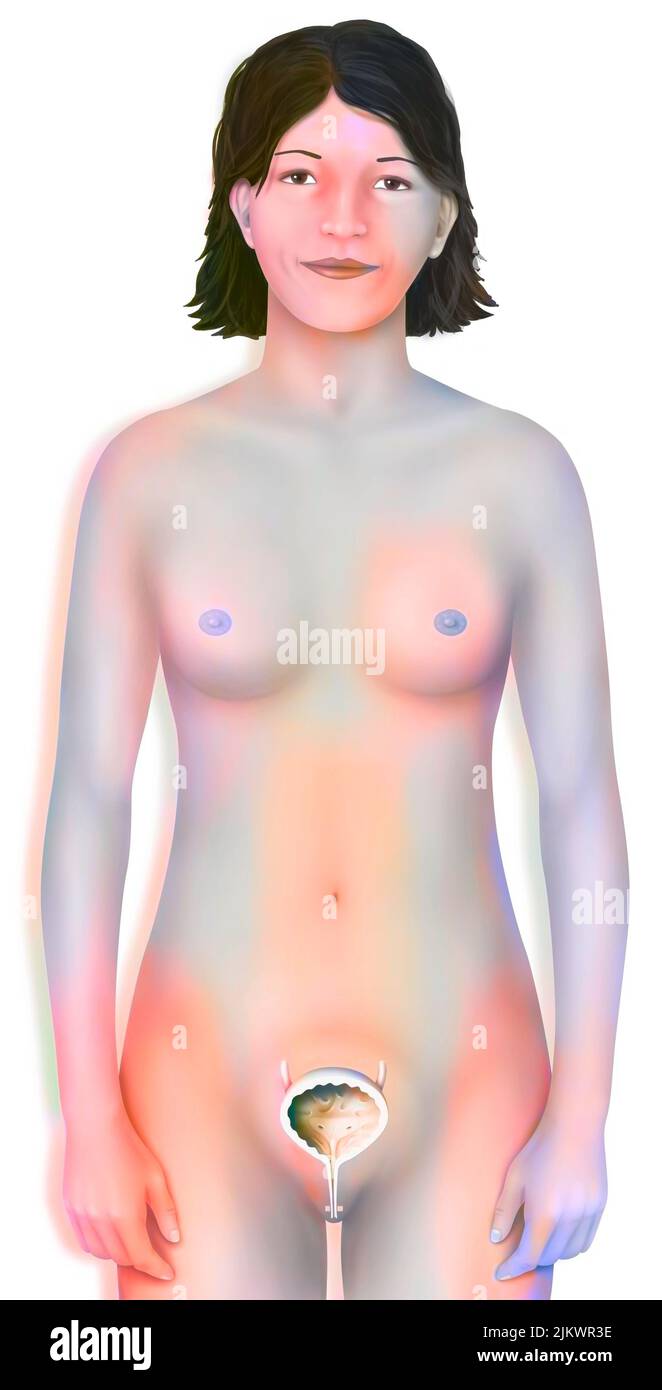

RF2JKWPFD–Auto-échantillonnage vaginal : l'écouvillon humide est administré au médecin pour analyse.

RF2JKWRM1–Vue antérieure des organes génitaux féminins avec vagin, utérus, trompes de Fallope, ovaires.